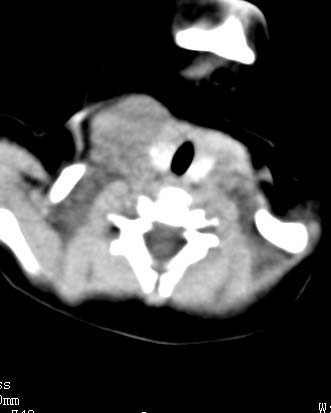

以下是引用zjzjr在2008-12-18 11:20:00的发言:[br]右颈部软组织肿块,性质待定(神经源性肿瘤等排),上下径较长,不太支持肿大淋巴结.